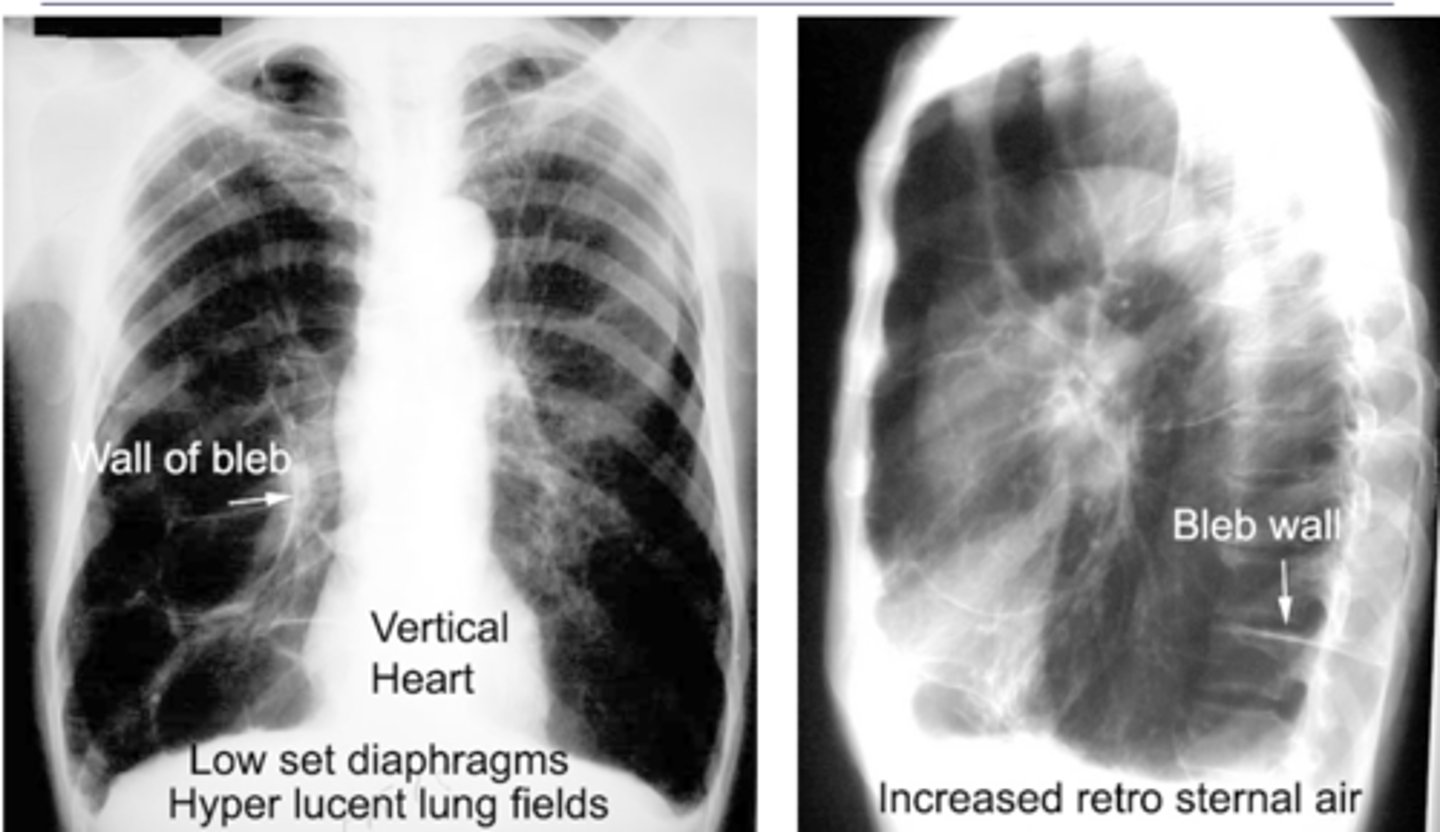

o Both terms refer to lung tissue with air space but no alveoli – (non-functioning).

o Bleb = less than 1 cm diameter

o Bullae = greater than 1 cm but often much larger

o Walls of lesion are very thin (often invisible)

o Difficult to see on CXR – can be seen as absence of pulmonary markings.

o Easy to see on CT scan.

Often associated with COPD or emphysema but bullae can be present in normal asymptomatic patients. (this pt has emphysema)

What dz are blebs and bullae associated with?

-Flattening of hemidiaphragms with blunting of costophrenic angles.

-Increased AP diameter of chest on lateral view (barrel chest)

-Presence of bullae or large air cavities

Flattened diaphragms, ant mediastinal space increased --> COPD/emphysema

Dx and ID radiological findings

<p>Dx and ID radiological findings</p>